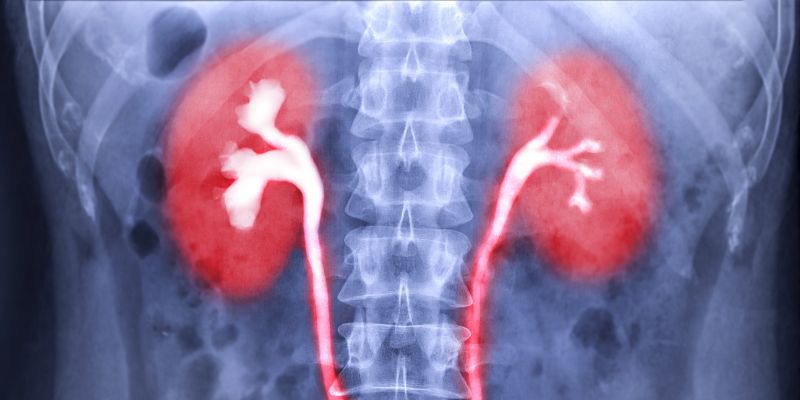

The kidneys are the stars of the show. They filter your blood, removing waste and extra water to create urine. The ureters are like pipelines, carrying urine from the kidneys to the bladder. The bladder is a storage tank, holding urine until you’re ready to let it go. Finally, the urethra is the exit path for urine to leave your body. Understanding these parts helped me see how everything connects, and it’s the foundation for explaining how urine ends up in the bladder.

Let’s start with the kidneys, because that’s where the whole process kicks off. I was blown away when I learned how hardworking these bean-shaped organs are. You’ve got two kidneys, one on each side of your spine, just below your ribcage. Each kidney is packed with about a million tiny filters called nephrons.

After the kidneys make urine, it needs to get to the bladder. That’s where the ureters come in. I remember picturing them as narrow tubes, like straws, connecting each kidney to the bladder. You have two ureters, one for each kidney, and they’re about 10-12 inches long in adults.